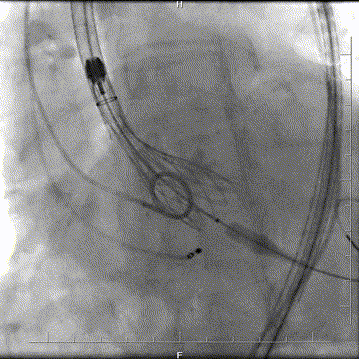

瓣膜定位

定位释放

完全释放